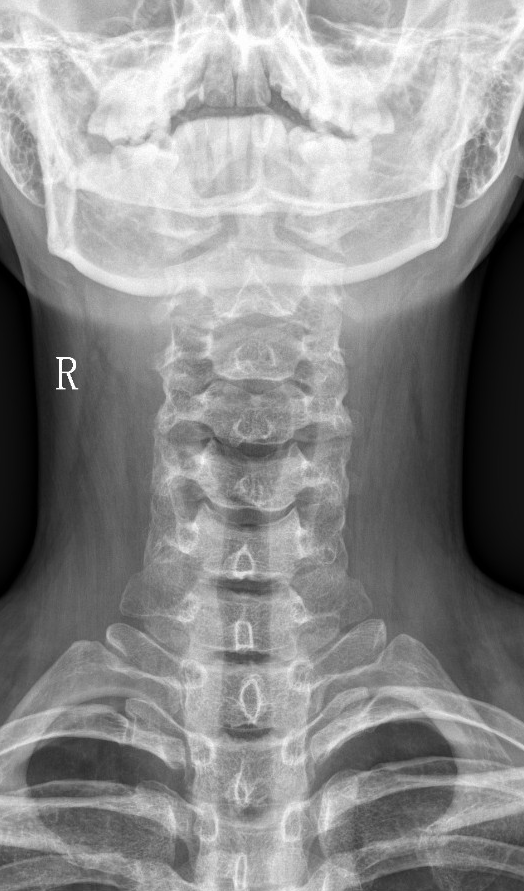

【影像】广州中医药大学深圳医院MR示:C5-6间盘膨出,L4-5间盘突出。X线示颈椎反弓伴侧弯,寰齿侧间隙右宽左窄,寰椎左侧侧块小。

【诊断】颈椎病;寰枢椎半脱位;